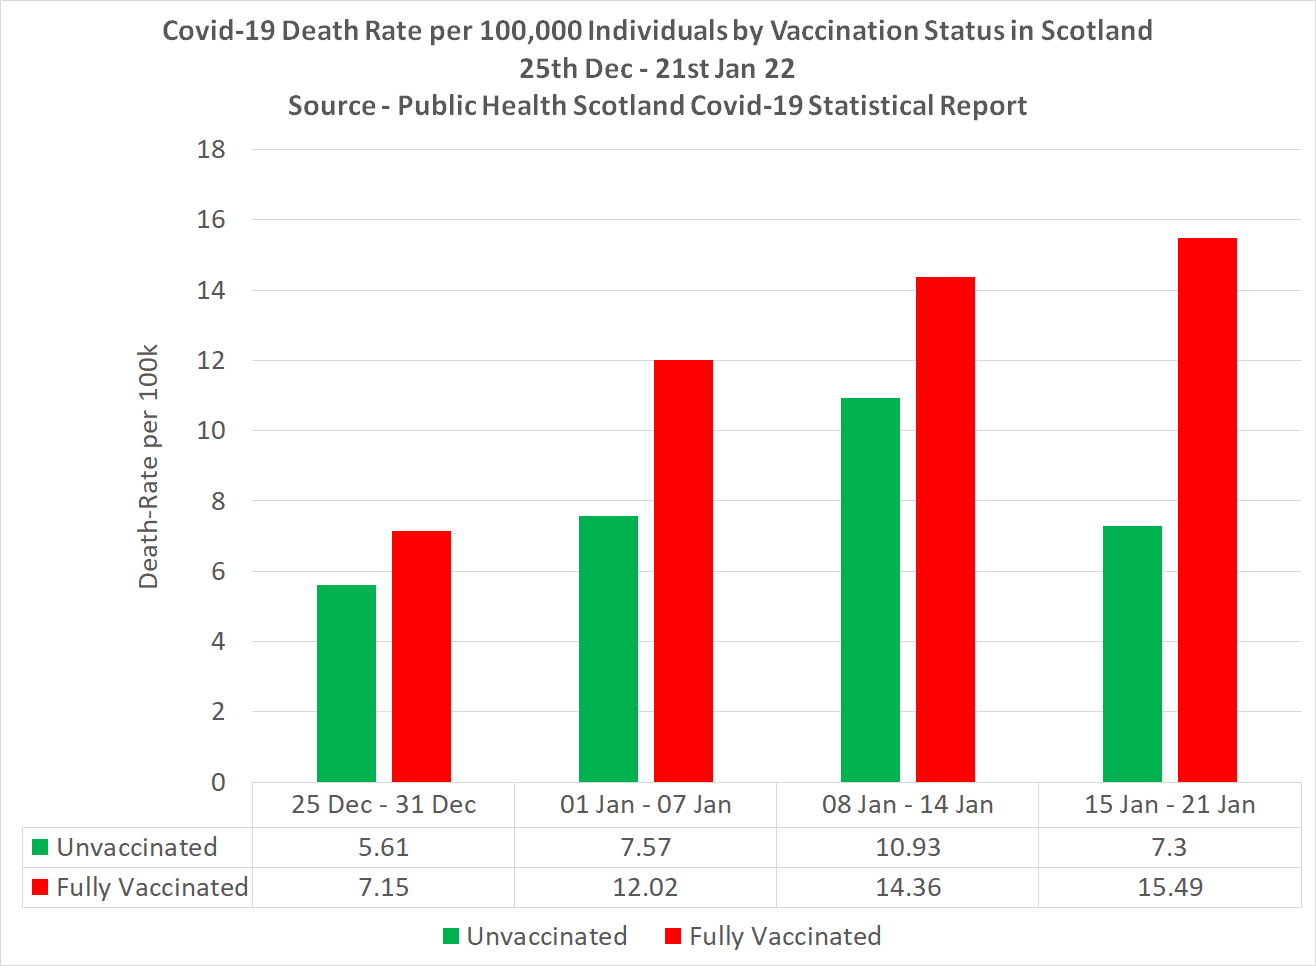

https://dailyexpose.uk/2022/02/04/covid-vaccine-effectiveness-against-death-minus-112-percent/

Read article